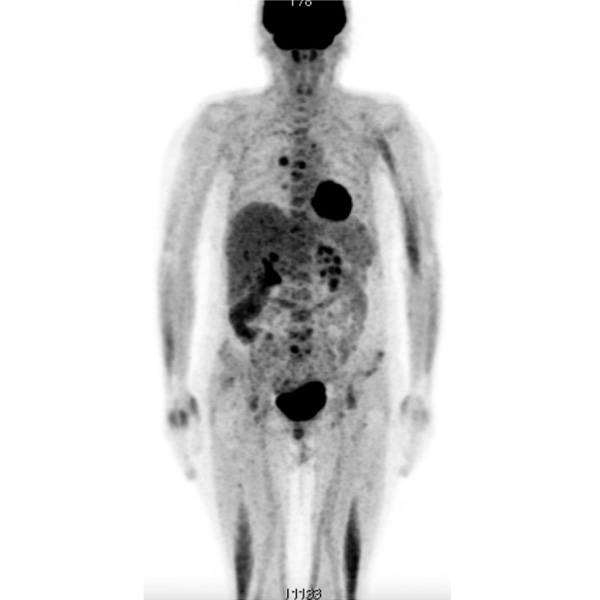

После 2 лет лечения (10.2017) для оценки метаболической активности и жизнеспособности остаточной опухоли выполнено повторное ПЭТ-КТ всего тела (рис. 6), по данным которого очагов патологического накопления радиофармпрепарата не выявлено. Таким образом, зарегистрирован полный метаболический ответ.

Рис. 6. ПЭТ-КТ всего тела от 10.2017 г.